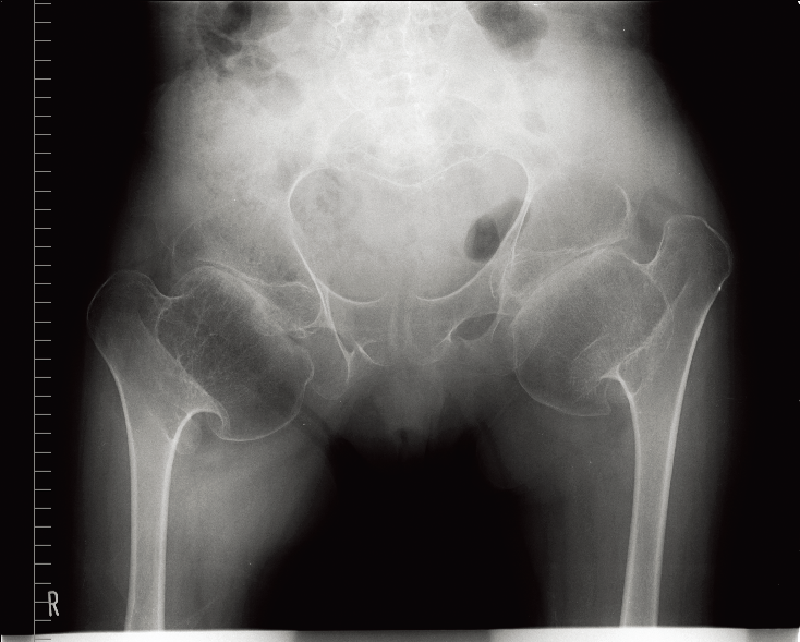

特徴的な画像所見:腸骨稜の不規則なレース様所見(lace-like appearance)が特徴的である(A)。脊椎は中等度の扁平椎を呈し、側面像ではひょうたん状の椎体変形(double hump)を認める(B)。長管骨では骨端異形成が著明で、特に大腿骨頭の骨化は遅延する。

Alquraishi AS, et al. Cureus. 2025; 17 (2): e78881.

(https://creativecommons.org/licenses/by/4.0/)

A. 両股関節正面像(8歳、男):腸骨稜のレース様所見と大腿骨頚部の短縮を認める。